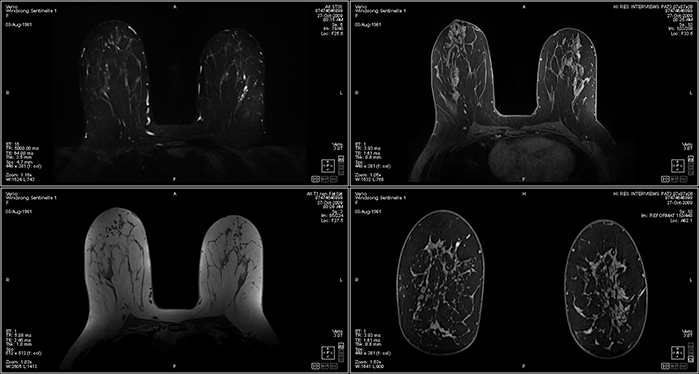

Product Brochure and MRI Sample Image

MRI Image Produced by this System